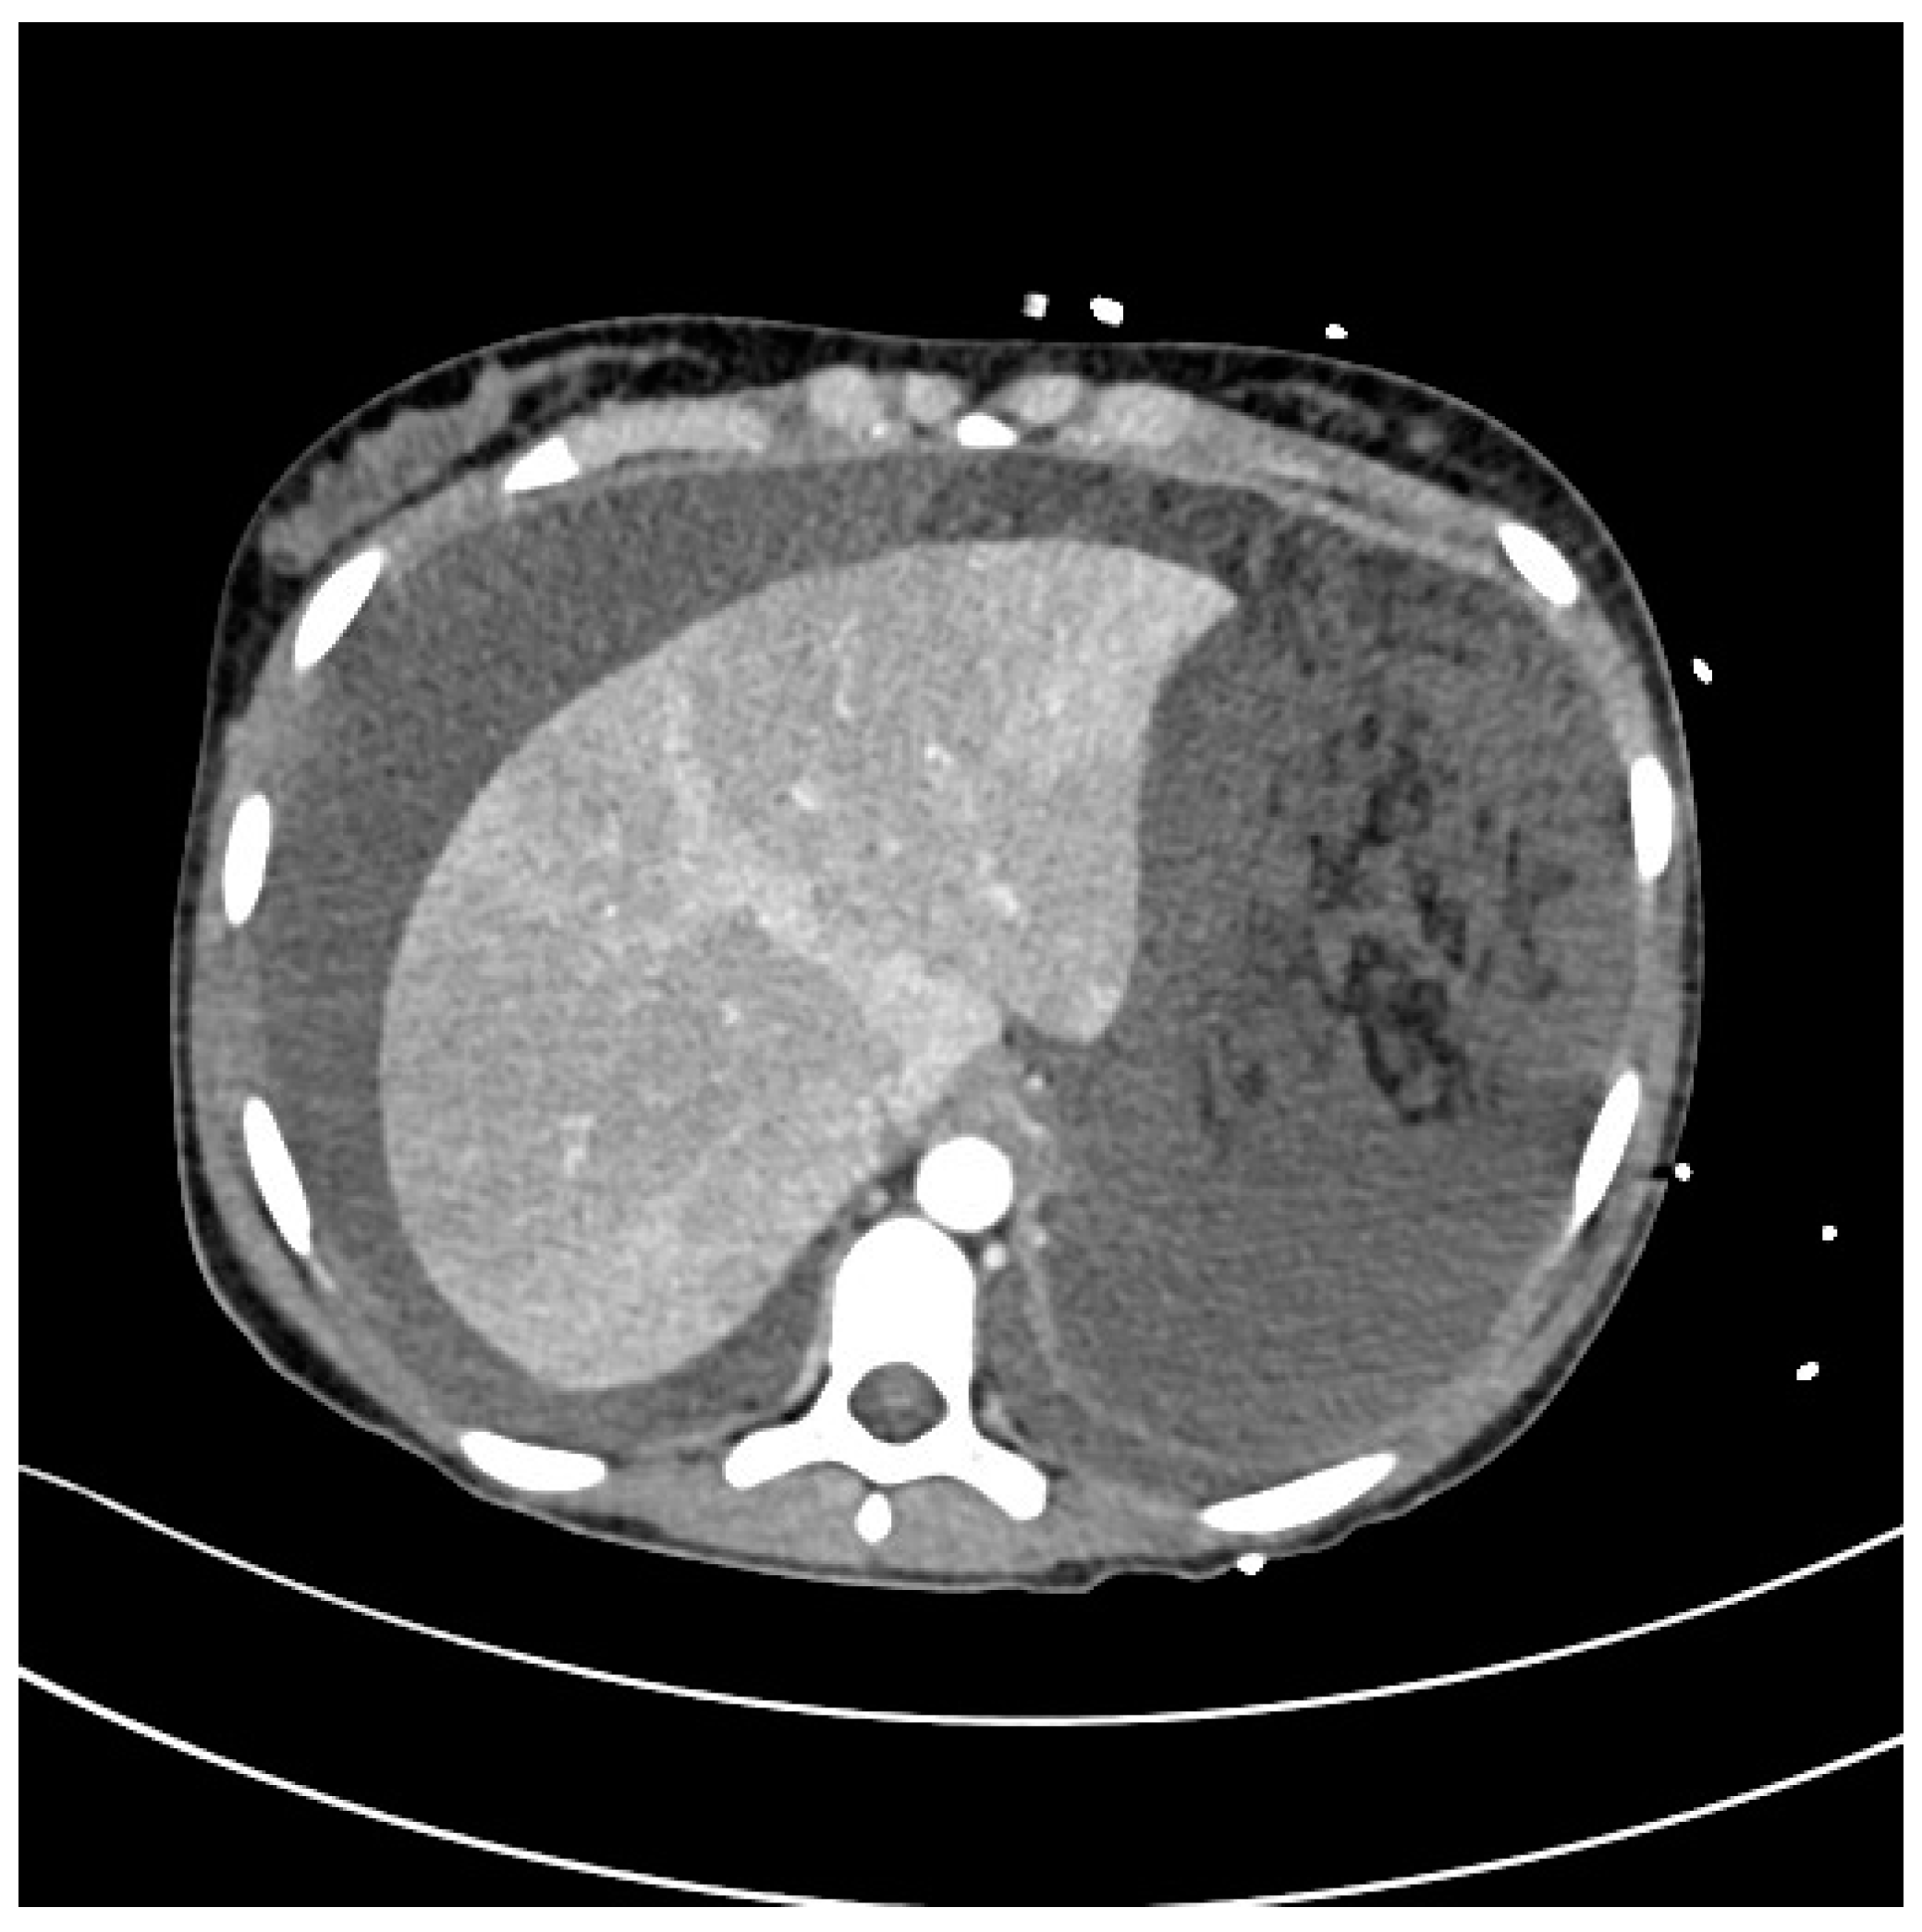

Severe Typhoid Fever Complicated by Superior Mesenteric and Splenic Vein Thrombosis

2. Case Description